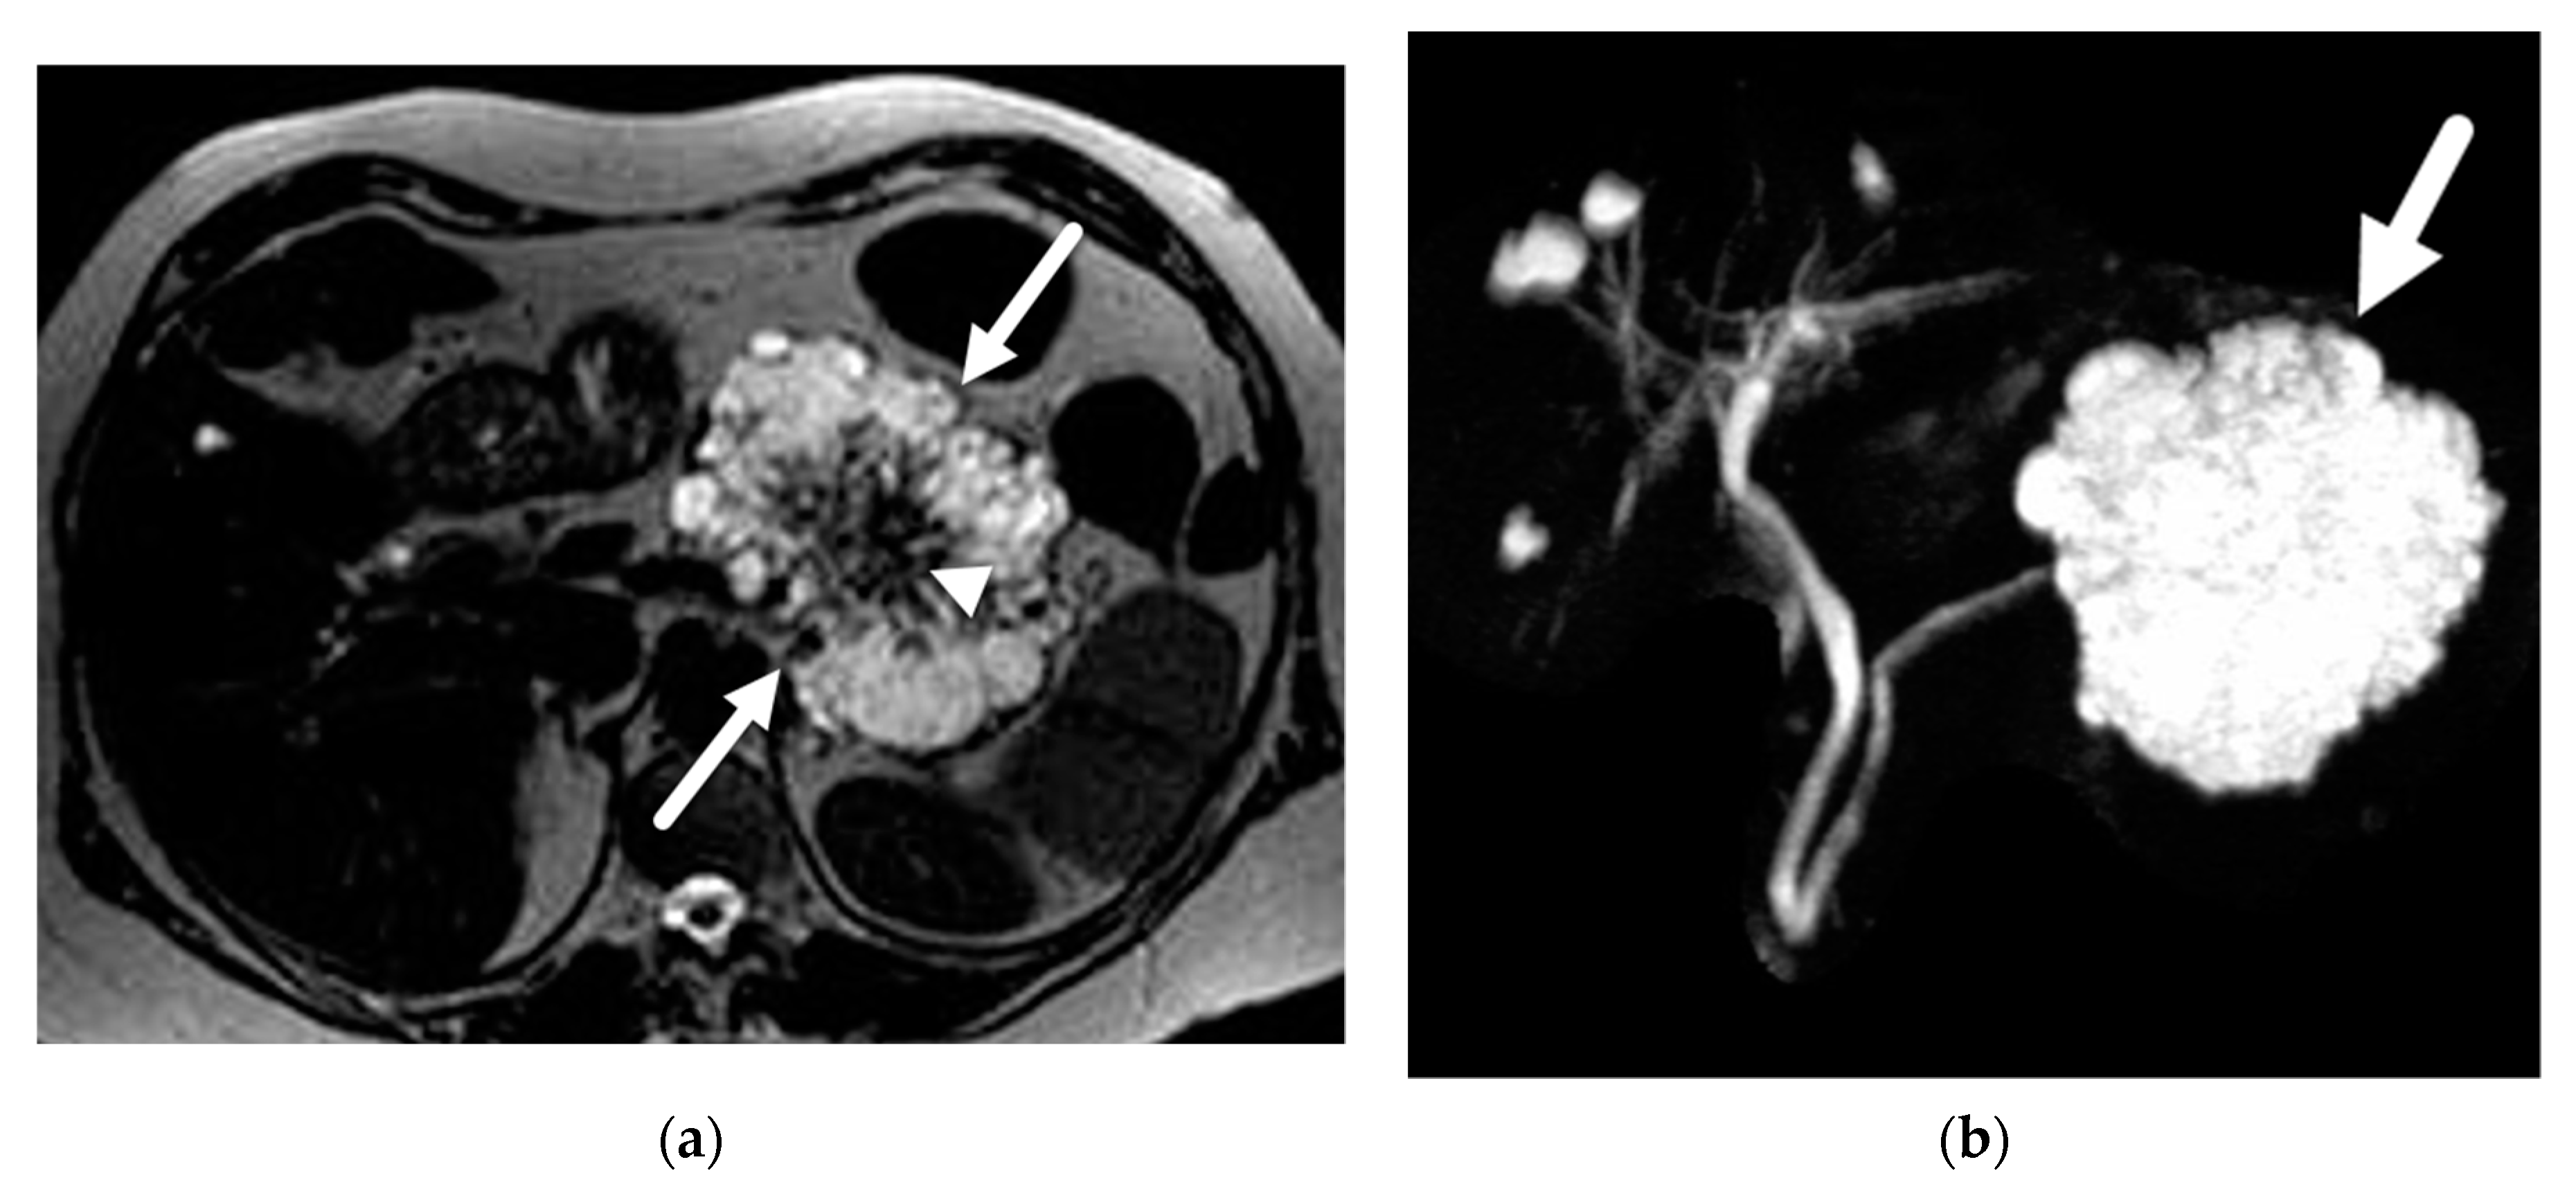

- Cantisani, V.; Mortele, K.J.; Levy, A.; Glickman, J.N.; Ricci, P.; Passariello, R.; Ros, P.R.; Silverman, S.G. MR imaging features of solid pseudopapillary tumor of the pancreas in adult and pediatric patients. AJR Am. J. Roentgenol. 2003, 181, 395–401. [Google Scholar] [CrossRef]

- Yu, M.H.; Lee, J.Y.; Kim, M.A.; Kim, S.H.; Lee, J.M.; Han, J.K.; Choi, B.I. MR imaging features of small solid pseudopapillary tumors: Retrospective differentiation from other small solid pancreatic tumors. AJR Am. J. Roentgenol. 2010, 195, 1324–1332. [Google Scholar] [CrossRef]